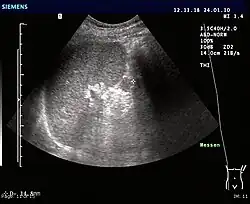

Ultrasonography of an accessory spleen.

An accessory spleen is a small nodule of splenic tissue found apart from the main body of the spleen. Accessory spleens are found in approximately 10 percent of the population[1] and are typically around 1 centimeter in diameter. They may resemble a lymph node or a small spleen. They form either by the result of developmental anomalies or trauma.[2] They are medically significant in that they may result in interpretation errors in diagnostic imaging[2] or continued symptoms after therapeutic splenectomy.[1] Polysplenia is the presence of multiple accessory spleens rather than one normal spleen.

If splenectomy is performed for conditions in which blood cells are sequestered in the spleen, failure to remove accessory spleens may result in the failure of the condition to resolve.[1] During medical imaging, accessory spleens may be confused for enlarged lymph nodes or neoplastic growth in the tail of the pancreas,[5] gastrointestinal tract, adrenal glands or gonads.[2]